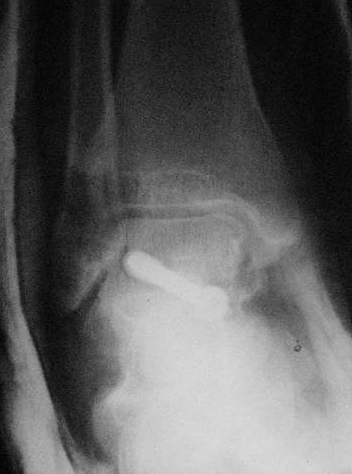

Второй случай прооперирован вчера.

10 дней назад поступил с открытым повреждением медиальной лодыжки и переломо вывихом таранной кости. Ургентно сделана репозиция с наложением наружного фиксатора + Irrigation&Debridment.

Во время репозиции выявили повреждение заднего сухожилия м. тибиалис и задней большеберцовой артерии. Медиальную рану удалось закрыть частично и установлен вакуум.

Дважды провели Irrigation&Debridment с заменой вакуума.

Вчера провели фиксацию.

Из-за многооскольчатости дистальной части малоберцовой, где невозможно было провести фиксацию шурупами, перелом зафиксирован подпирающей пластиной, которая должна служить дополнением отсутствующей дистальной части малоберцовой (lateral cortex substitute).

Для стабильности два шурупа на синдесмоз.

Медиальную рану с приближенными краями продолжаем вакуумировать (KCI). Наружный фиксатор оставлен на пару недель, надеюсь, небольшая рана будет гранулировать и закроется без кожной пластики. Фиксация медиальной ложыжки не планируется.